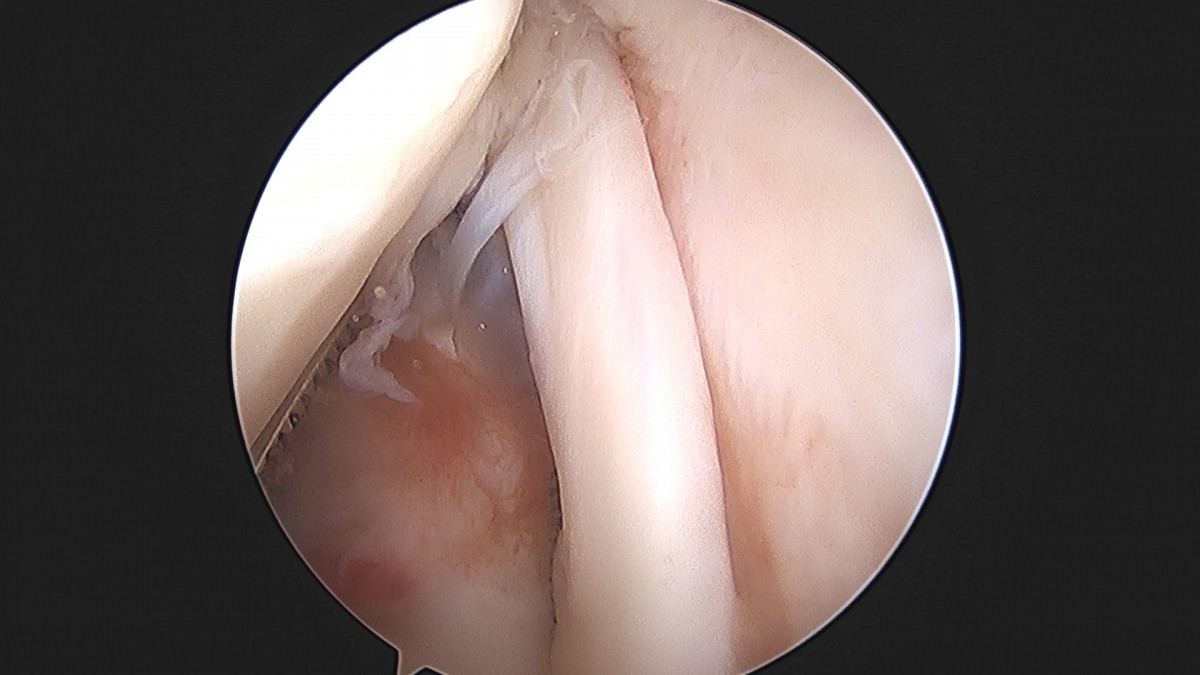

이재상원장님 어깨 견봉하 감압술 및 관절낭 이완술 주혜O 환자

dae765e4d9ac96aee867c9d6292d8784_1758003912_2111.jpg